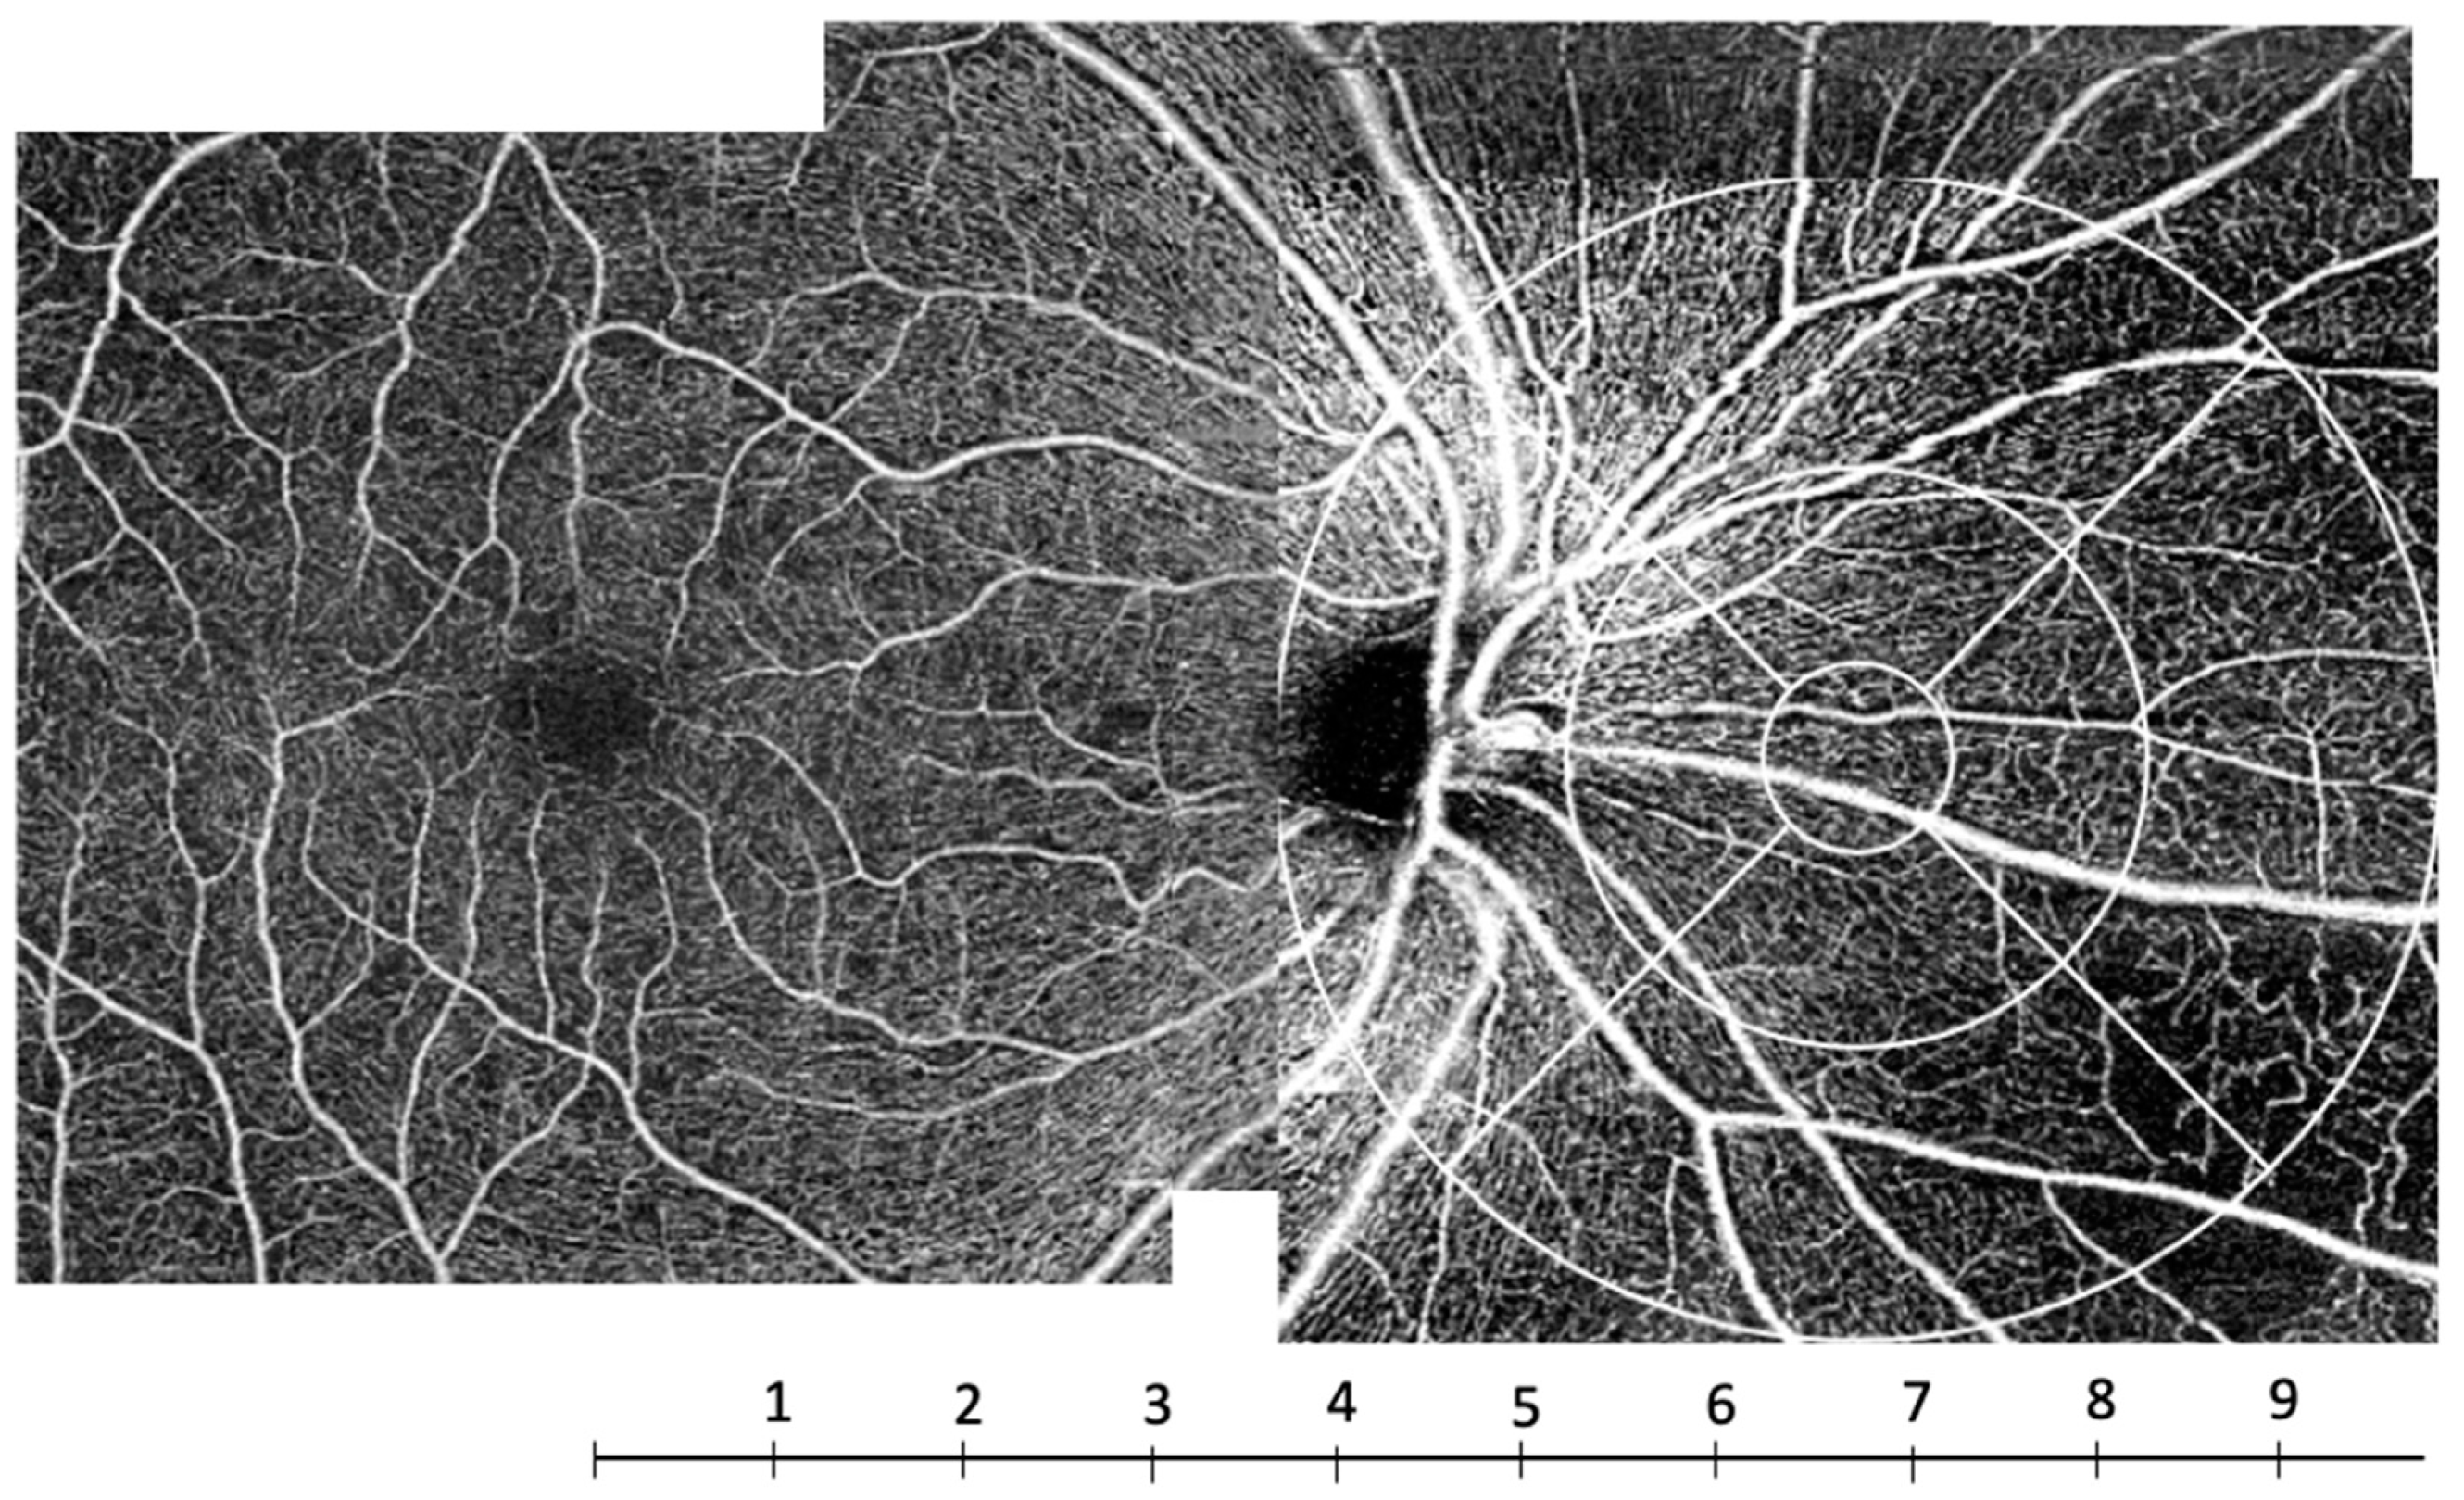

Such a decrease in capillary density in the periphery has already been described in healthy subjects. Carlo Lavia et al. have shown a decreased density in the periphery of the SCP at about 8 mm from the fovea in healthy subjects. This location corresponds to the area where the intermediate capillary plexus vanishes in the periphery [21]. This threshold of 8 mm (about 8 mm temporally and 10 mm nasally, if the optic nerve head is not taken into account) corresponds to zones 6, 7 and 8 of the grid used in our study (Figure 8), that is, the outermost zones of the ETDRS grid moved nasally (Figure 2 and Figure 8). Thus, this peripheral zone could be more vulnerable to ischemia.

Figure 8.

OCTA C-scan montage of the superficial capillary plexus (SCP) in a subject with severe non-proliferative diabetic retinopathy. The scale under the image indicates the distance to the fovea in millimeters. The capillary rarefaction predominated at a distance of about 8 mm from the fovea corresponding to zones 6, 7 and 8.